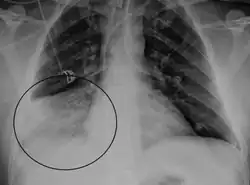

Una radiografía de tórax o una broncoscopia también se utilizan para buscar cambios o neumonía en las vías respiratorias de los pulmones.[22]